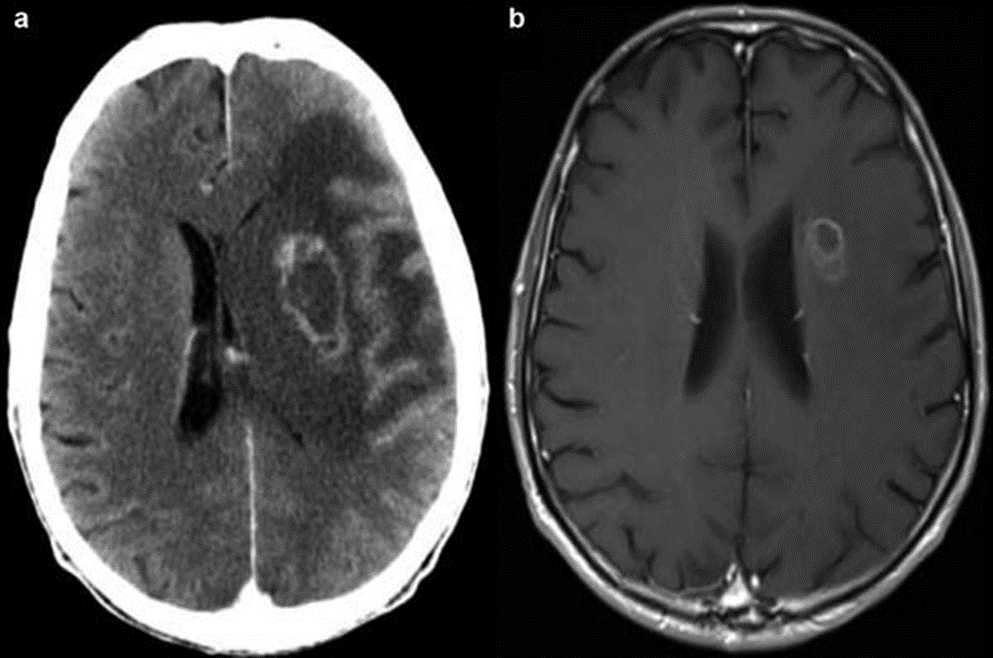

A thread on brain parasites that CANNOT be treated with ivermectin

🧡 https://link.springer.com/referenceworkentry/10.1007/978-1-4614-9610-6_405-1